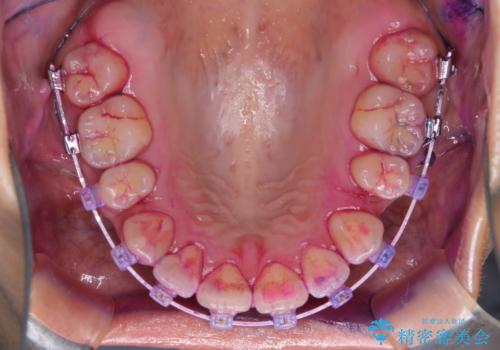

ワイヤー矯正中のクリーニング

- ワイヤー矯正中に、磨ききれないところがあるのと、口臭が気になるとのことでした。

そのためPMTC30分コースを行いました。

ワイヤー矯正中は、装置の周りに汚れが付きやすく虫歯や歯周病のリスクが高まります。そのため、ワイヤー調整の診察の際、一緒にクリーニングを行うことで、虫歯・歯周病・口臭予防になります。歯ブラシだけでは取り除くことが難しい細かい部分などに、専門的な機械や機材を使用して定期的なケアを行うことをおすすめしています。